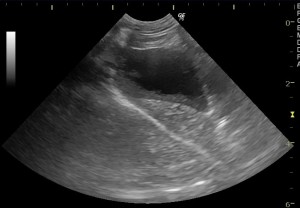

胆嚢粘液嚢腫の子の超音波画像です。画像の左に位置しているのが膨れ上がった胆嚢です。胆嚢の内壁部分の黒く抜けて見える部分は胆汁ではなくムチンで、その中心の白くなっている部分が濃縮された胆泥です。